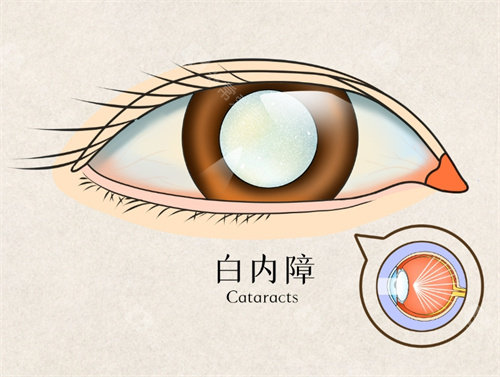

白内障正规开展了多种白内障手术,包括超声乳化白内障吸除术等,手术技术成熟,术后结果良好。